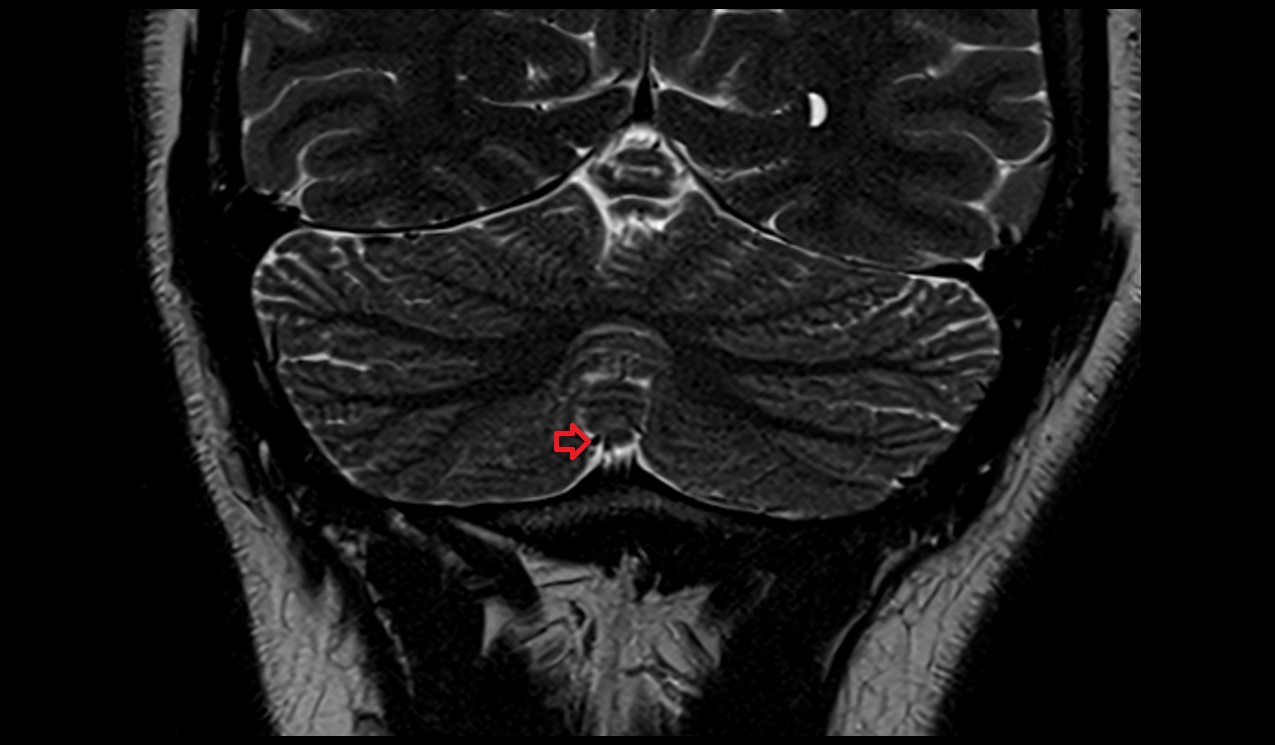

- Median aperture of fourth ventricle (foramen of Magendie)